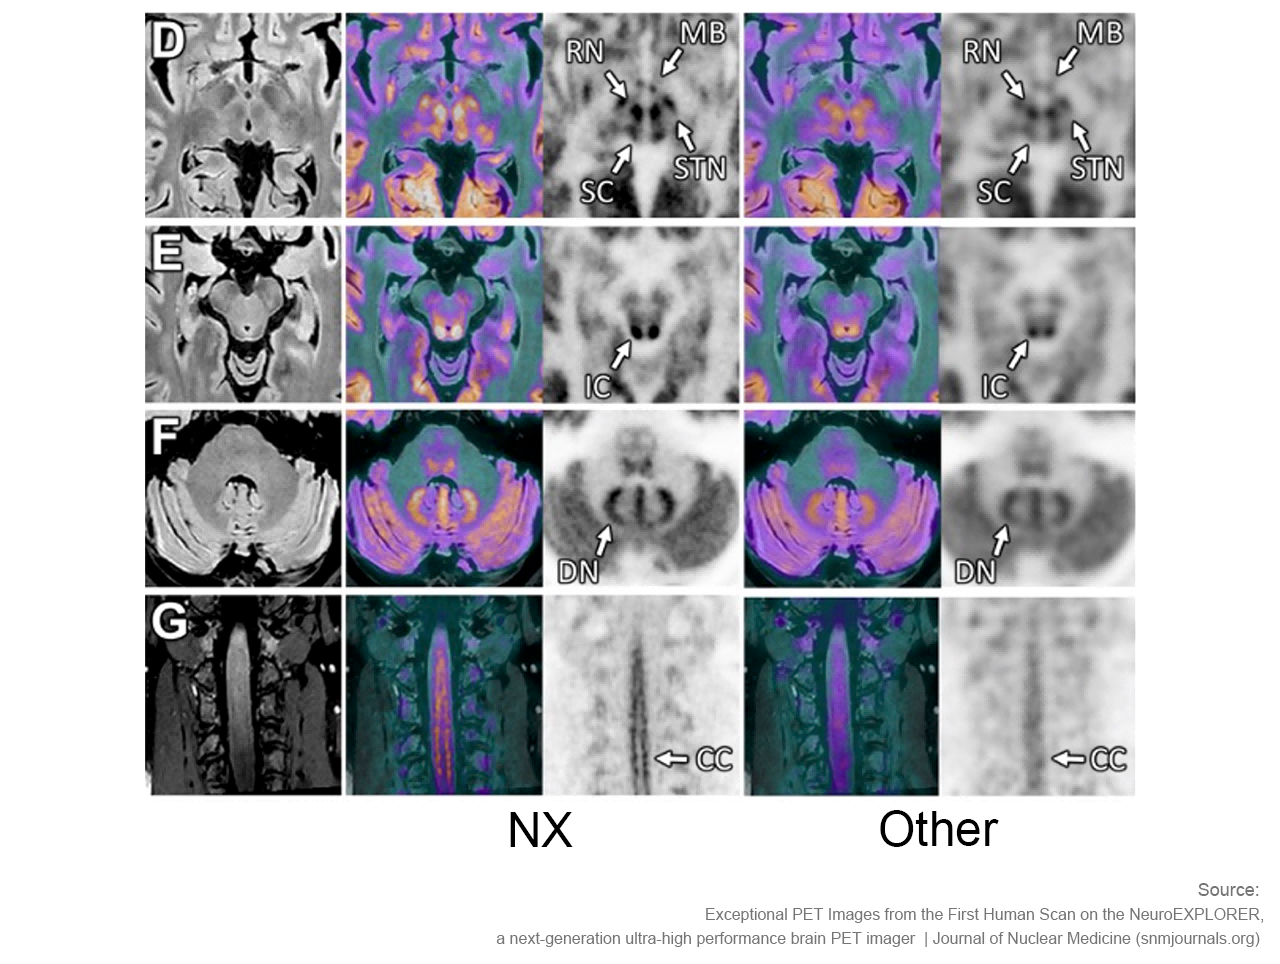

卓越空间分辨率 洞察大脑微观

小型探测器元件确保最精微的结构能被检测,甚至探查特定脑核中的神经递质运动。搭载1.5mm的有效空间分辨率,带来前所未见的解剖细节。

NeuroExplorer (NX)产出的脑部影像图与其他设备产出的脑部影像图对比

“从我们目前获取的图像来看,使用NeuroExplorer扫出的图像是世界上最好的,因此我们能够真正做到更好地缩小范围,聚焦更小的信号,观察大脑更为微末的区域,这为我们打开了新的窗口,去‘见所未见’。”Carson教授对NX的诞生和即将围绕其展开的一系列研究满怀期待,“有了NeuroExplorer这样强大的设备,我们步履不停,也正将迎来一个重要的突破,那就是和制药行业的合作。”